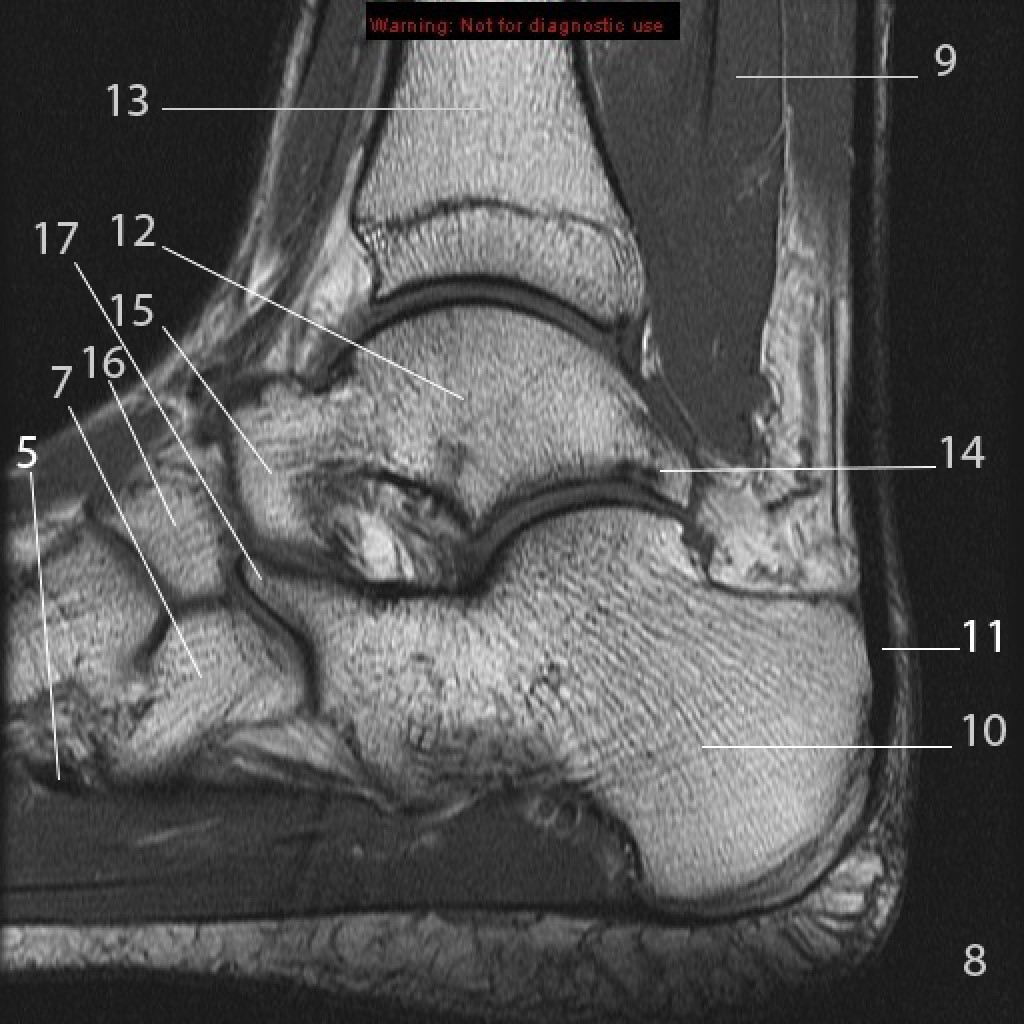

Анатомия голеностопа: Сухожилия и их строение